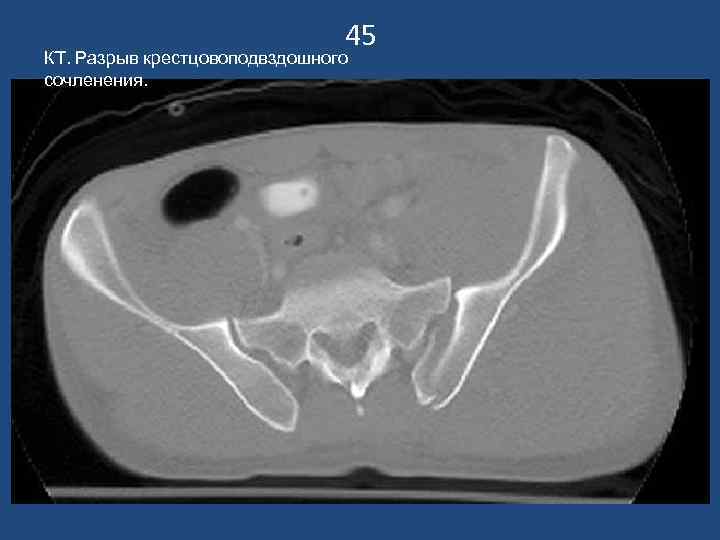

45 КТ. Разрыв крестцовоподвздошного сочленения.